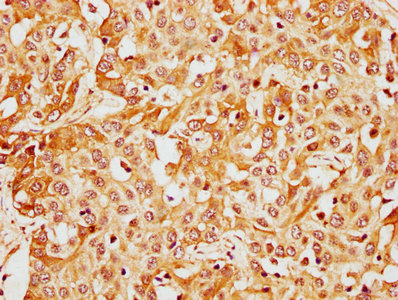

IHC image of CSB-PA13809A0Rb diluted at 1:400 and staining in paraffin-embedded human liver cancer performed on a Leica BondTM system. After dewaxing and hydration, antigen retrieval was mediated by high pressure in a citrate buffer (pH 6.0). Section was blocked with 10% normal goat serum 30min at RT. Then primary antibody (1% BSA) was incubated at 4°C overnight. The primary is detected by a biotinylated secondary antibody and visualized using an HRP conjugated SP system.